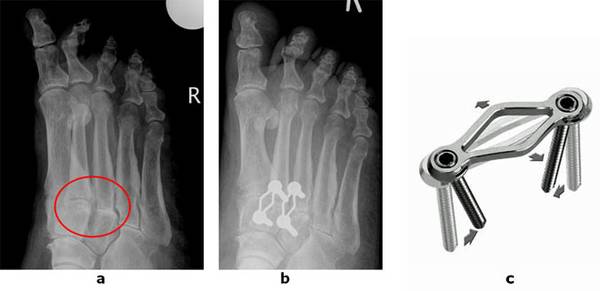

Abb.1 a: Arthrose zwischen Mittelfuß und Vorfuß (TMT Gelenk) b: Fusion des Gelenkes mit einer Spezialplatte

c: Die verwendete Stabilisierung erlaubt einen minimalinvasiven Zugang. Das Klammer/Schraubensystem erlaubt eine maximale Kompression auf den Fusionsspalt und verbessert die Heilungsrate.